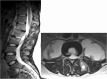

Recent findings: Recent studies have focused on risk factors for failed nonoperative management in order to improve patient selection. Also, spine instrumentation and different grafting options have been safely utilized in the setting of an active infection without increasing the incidence of reoccurrence. However, the optimal surgical technique has yet to be established and instead should be patient specific. Spine infections include a broad spectrum of disorders including discitis, vertebral osteomyelitis, and spinal epidural abscess. It is paramount to recognized spine infections early due to the potential catastrophic consequences of paralysis and sepsis. The management of spine infections continues to evolve as newer diagnostic tools and surgical techniques become available. Magnetic resonance imaging with contrast is the imaging study of choice and computed tomography-guided biopsies are crucial for guiding antibiotic selection. Antibiotics are the mainstay of treatment and surgery is indicated in patients with neurological deficits, sepsis, spinal instability, and those who have failed nonoperative treatment.